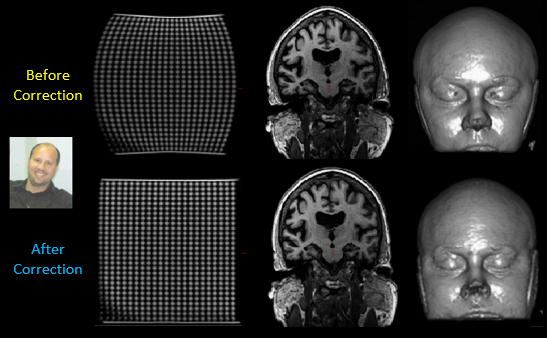

When using Cortechs.ai’ NeuroQuant® and PETQuant™ products, head alignment and slice presentation are automatically corrected for magnetic field inhomogeneity and non-cardinal patient positioning, providing consistency and reproducibility from scan-to-scan, site-to-site and in follow-up patient scans, without operator intervention. (Example below.)

Correction of spatial distortion

MR images inherently contain spatial distortions due to magnetic field properties of the magnet, magnetic field inhomogeneity introduced by the patient’s body, and inhomogeneous tissue magnetization. Cortechs.ai automatically corrects for these spatial distortions, allowing for improved spatial integrity of the derived images generated by NeuroQuant and PETQuant. (Example below.)